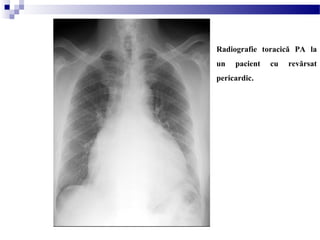

REVĂRSATUL PERICARDIC

- Revărsatul pericardic produce o lărgire a siluetei cardiace care este

adesea de formă globulară (diametrul transvers dispropor ional crescut).ț

- Radiografiile seriate pot fi utile diagnosticului în special când sunt

observate schimbări rapide ale mărimii siluetei cardiace;

- Sunt necesari aproximativ 400-500ml de lichid pericardic pentru a fi

detectată o schimbare a mărimii siluetei cordului pe o radiografie toracică

PA;

- Diagnosticul de certitudine poate fi pus de ecocardiografie sau CT

Radiografie toracică PA la

un pacient cu revărsat

pericardic.